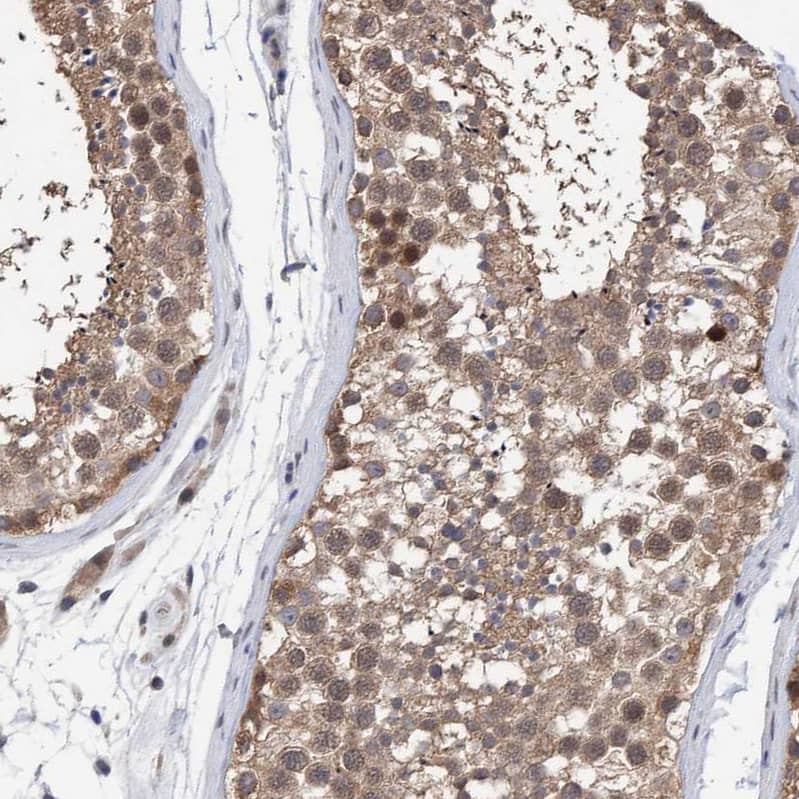

NBP1-84691

(2 Publications)

Species:

Hu, Mu, Rt

Applications:

WB, ICC/IF, IHC

Host:

Rabbit Polyclonal